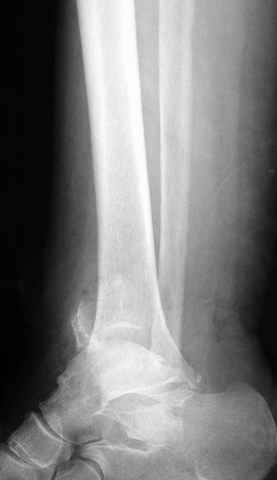

Re: ANKLE FRACTURE

Я вот все в толк не возьму смысл отдельной фиксации малоберцовой кости пластинкой, если все равно будет аппарат с фиксацией стопы, т.е. возможностью провести спицы в пятку, таран, наружную лодыжку и еще черт-те куда. Остеосинтез пластинкой выглядит логичным в случае, когда наружная фиксация планируется как временная. Но тут-то аппарат будет окончательным фиксатором.

I can't realize why plate fibula separately if anyway external fixator including the foot is planned, i.e. one may insert wires to the talus, calcaneus, lateral malleolus and anywhere else. Plating looks reasonable if only temporary ex-fix is planned, but in the case it will be definitive.